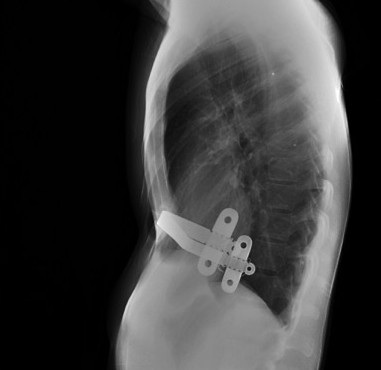

PECTUS EXCAVATUM.

Con una frecuencia de 8 por 1.000 recién nacidos vivos, constituye la más común de las deformidades congénitas de la pared anterior del tórax. Suele estar presente al nacer o comienza a evidenciarse durante el primer año de vida, acentuándose en la adolescencia. Predomina en varones 3:1 y pueden existir antecedentes familiares.

Es una depresión esternal interna, formando una concavidad, consecuencia de una anormalidad en el crecimiento del esternón y de los cartílagos costales. Suele ser asimétrica, de predominio derecho. Su etiología es desconocida aunque puede influir la tracción del diafragma.

Puede estar asociado escoliosis, Marfan, cardiopatía congénita, displasia broncopulmonar, enfermedades metabólicas o del tejido conectivo.

Suele ser asintomáticos. En casos de deformidades acentuadas, pueden causar dificultad respiratoria. La presencia de sintomatología debería hacer plantear un protocolo de estudio rápido.

El diagnóstico es clínico. Con la imagen evaluamos mejor la deformidad, útil en caso de ser necesaria la cirugía.

En la Rx de tórax se observa el borramiento del borde cardiaco derecho y en la placa lateral, la depresión interna del esternón, característicamente del cuerpo esternal y de la apófisis xifoides. En casos más acentuados, el corazón, los pulmones, el esófago y el diafragma pueden estar comprimidos, con desplazamiento del corazón hacia la izquierda y prominencia del tronco de la arteria pulmonar en la proyección PA; hallazgos mas evidentes gracias al TC y las reconstrucciones.

El tratamiento puede ser conservador o eventualmente quirúrgico.

Índice de Haller:

- Medio: 3,2

- Moderado: 3,2-3,5

- Severo: > 3,5 (cirugía).